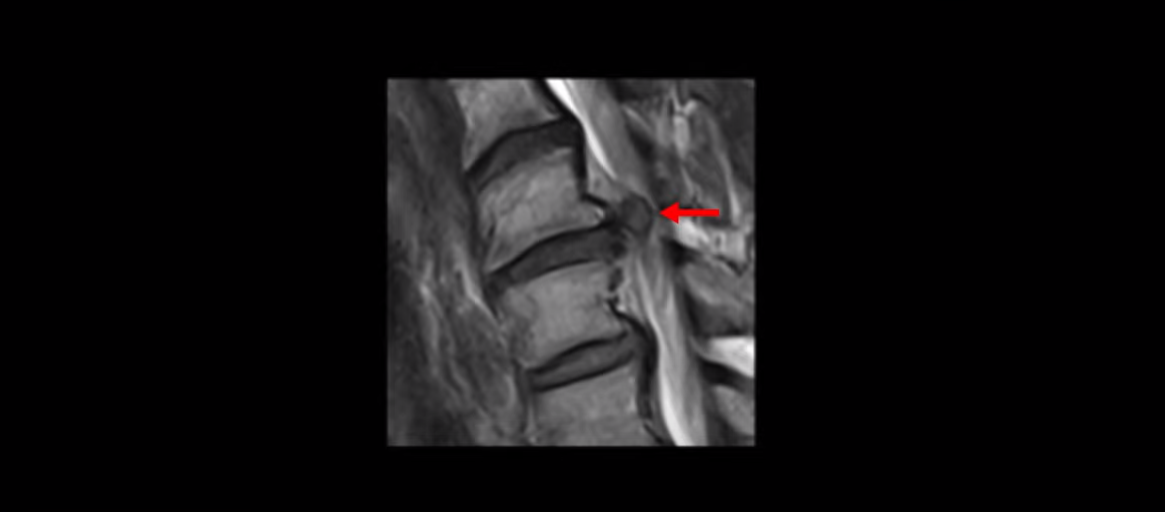

이분 목 MRI를 보면 6번, 7번 디스크에 매우 심한 디스크 파열이 있습니다.

이렇게 심하게 척수 신경을 누르니까 신경 손상이 생기고 척수증 증상이 발생하는 겁니다.